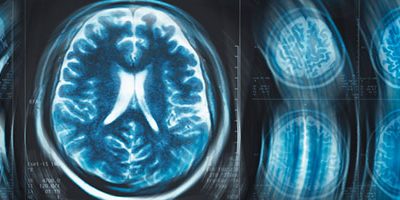

Совместный продукт Национального исследовательского ядерного университета «МИФИ» и Центра «Гамма-нож Москва» — программно-аппаратный комплекс для гарантии качества магнитно-резонансной томографии — позволит сделать проверки рутинными.